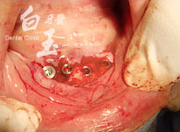

植入植體